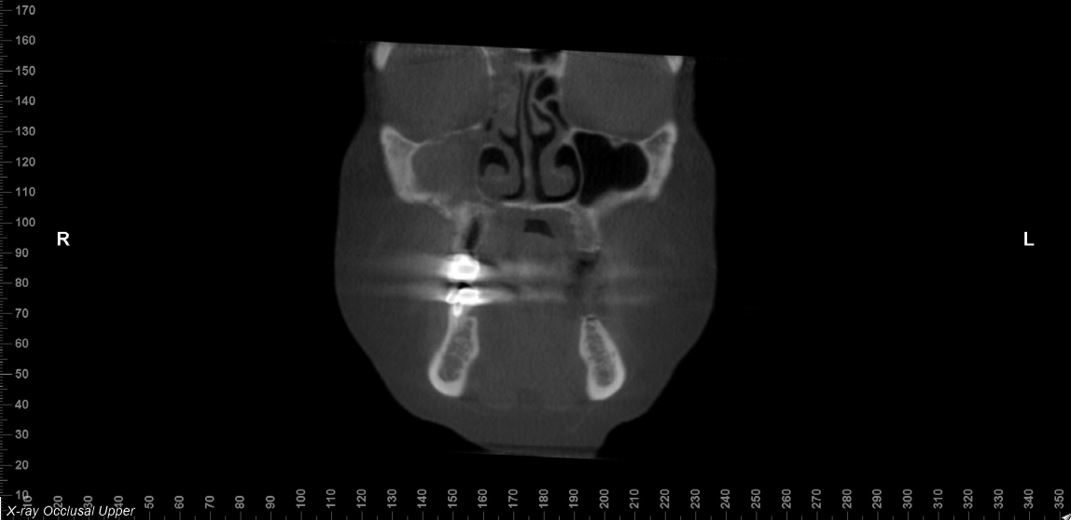

A total of nine patients (3 male, 7 female) were identified with a mean age of 70 years (range 59-88 years). All had received intravenous bisphosphonate or denosumab therapy (for malignancy in 8 cases, osteoporosis in 1). All patients presented with exposed bone in the maxilla and radiographic evidence of maxillary sinusitis (Figures 1,2). All underwent single-stage surgery combining MRONJ debridement/resection with endoscopic maxillary antrostomy. All 9 patients had a maxillary antrostomy; 7 also underwent ethmoidectomy, 1 had a frontal sinusotomy, and 1 had bilateral FESS. All patients achieved mucosal healing by 4 months postoperatively (Figure 3). Healing was maintained in all cases through final follow-up (up to 24 months). Two patients had persistent OAC, one of which underwent obturator insertion at the time of surgery due to the extent of the defect. No patients had persistent pain (all were pain-free at last follow-up) and none required long-term antibiotic therapy. All patients displayed complete resolution of sinus symptoms by 4 months (sinus pain, congestion, drainage). No patients had recurrence of exposed bone or sequestrum after healing (Table 1).

Figure 1. Pre-Operative Cone Beam Computed Tomography scan showing bony sequestrum of right maxilla with right maxillary and ethmoid sinus opacification